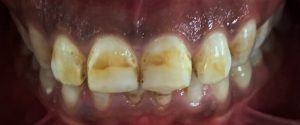

Department deals with all the treatments of teeth which alleviate pain due to pulp diseases and provide immediate solace to the patient. It also deals with the esthetic rehabilitation of the discolored, broken, mutilated teeth. Advanced endodontic treatment including micro-endodontics and regenerative therapy are also performed. Our department aims at creating and achieving excellence in the field of research and scientific development.

TREATMENTS

SERVICES